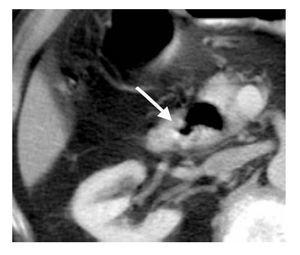

En siete casos (14%) el Dd causaba un efecto de masa sobre estructuras adyacentes (rango de diámetro de 2.1 a 7.1 cm). Además, el Dd fue condicionante de pseudolesión focal en la cabeza pancreática en 14 casos (28%). Se identificaron tres casos (6%) de Dd yuxtapapilar, uno de ellos que se complicó con sangrado del tubo digestivo y fue el de mayores de dimensiones (7.1 cm por 4.4 cm). No se identificaron Dd asociados a coledocolitiasis (Figura 4).

¿ Figura 4. Imágenes axiales, fase con contraste oral, en una mujer de 75 años con hallazgo incidental de gran Dd único, complicado con sangrado digestivo alto, yuxtapapilar, de 7 cm, ubicado en la segunda porción de duodeno (zona periampular).